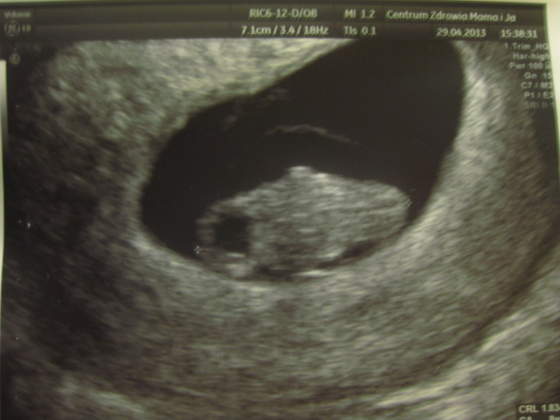

yyyy.. fajny tekstwidziałam kilka razy swoja macicę i bardzo chciałabym zeby była już zajęta tak jak Twoja :-)